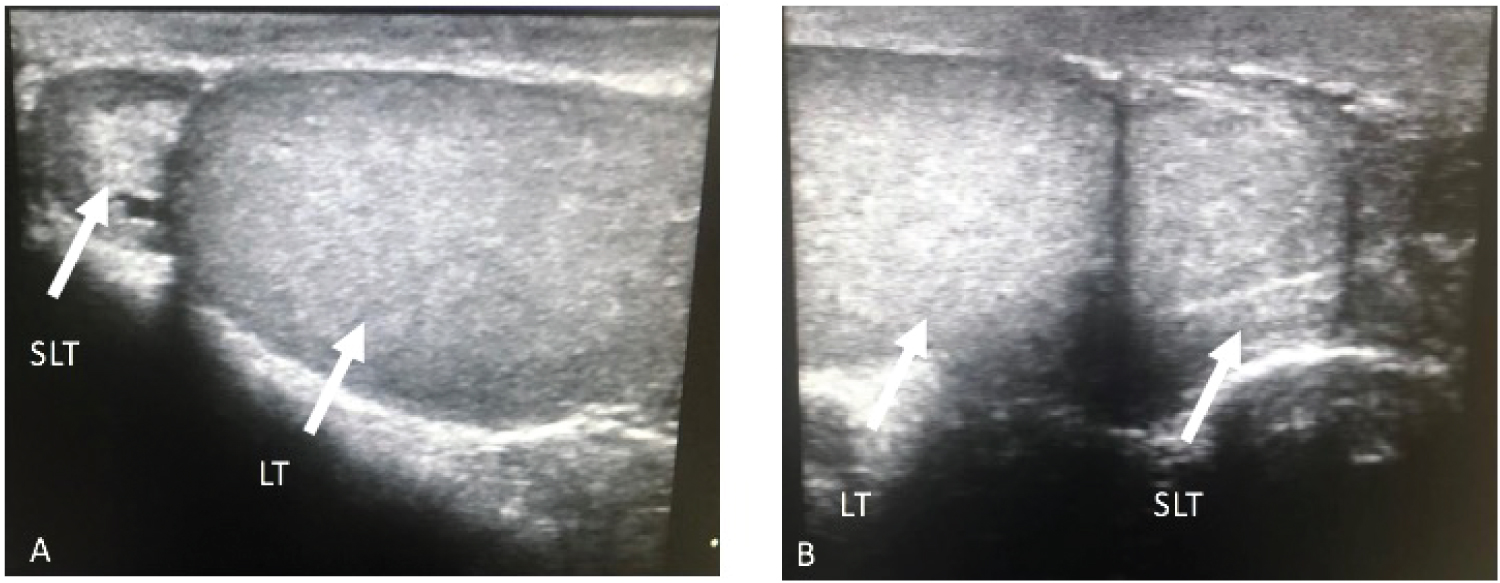

A healthy 23-year-old male showed to the outpatient clinic presenting a two-year-long left scrotal mass sensation and intermittent pain. A solid mass from the inferior pole of the left testicle was found palpated on physical examination. It was painless when palpated and independent from the epididymis. Testicular ultrasound was performed in the urology department, evidencing a left-sided testicle's lower pole round mass, with the same echogenicity as the rest of the testicle. The right testicle was normal, with dimensions of 50 × 31 × 33 mm with a volume of 27 cm3.The left testicle was 36 × 24 × 29 for 13 cm3, and the upper pole mass ipsilateral to the left testicle was 14 × 13 × 16 mm with a volume of 1.5 cm3 (Figure 1). Considering the findings suggesting a peritesticular mass, tumoral markers and a pelvic MRI were ordered.

Figure 1: US. LT, Left testicle. SLT, Supernumerary left testicle. SLT located in the upper pole of the LT, both with similar echogenicity. View Figure 1

Some authors argue that ultrasound alone is enough to make the final diagnosis [18]. However, a Doppler ultrasound or an MRI can also be helpful for diagnosis. The ultrasound will identify a scrotal mass identical to the ipsilateral testis on every ultrasonographic technique performed, as is shown in our case in Figure 1 [19]. The Doppler will report a mass separated from the testis with a gray-scale ultrasound pattern, showing similar echogenicity or slightly less echogenic than the normal testis, and provides information on the vascularity and viability of the gonad [20]. Meanwhile, on the MRI, a typical oval or round structure can be observed with the signal characteristics of the testicles: a homogeneous intermediate signal intensity on T1 and high intensity on T2. In some cases, the MRI will not provide additional information than the one found on the sonography. However, the MRI would play a confirmative diagnosis role [21].